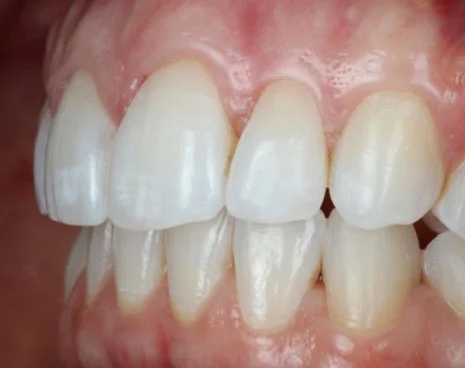

Our amazing Invisalign results

If you’re wondering whether Invisalign can really make a difference, simply take a look at these images below.

Case 5:

![]()